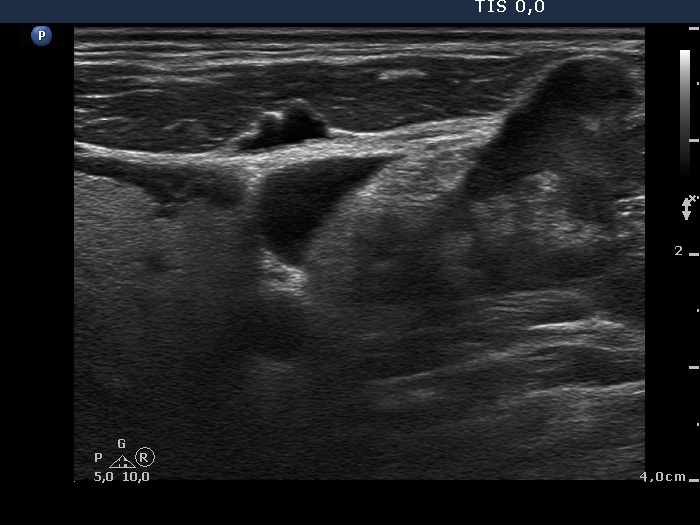

Lymph nodes in the neck - Case 154 (ultrasonographic picture 8)

Left lobe and left supraclavicular region, transverse scan. The intact left thyroid (left in the image) and a metastatic lymph node in the supraclavicular region (right in the image) in a common field of vision.